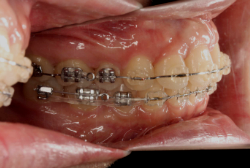

混合歯列期から治療開始した側方拡大による非抜歯症例

「配列の凸凹を治したい」という主訴で来院したケースです。診断の結果、永久歯がすべて生えそろうと、かなり厳しい叢生(歯並びの凸凹のことです)になる可能性が高いと判明しました。原因としては特に上の顎の骨が小さいため、歯を収容する容量不足になっていると診断しました。このケースの場合は、成長発育期に治療開始しますので、顎の骨を土台ごと大きくすることが可能です。

そこで、まず急速拡大装置を使用して上顎骨の拡大を行い、上顎骨の容量が拡大したことを確認後、マルチブラケット装置を使って全体の修正をする、と言う二段階の作戦をとることになりました。

この時期に使う急速拡大装置は、適切な診断に基づいて正しく使用することで確実に骨を大きくすることができます。拡大することで隙間が確保できるので、永久歯の抜歯を避けることができます。

急速拡大装置を1日1回装置の中央にある拡大ネジを、ご自身で回して頂くことで25日間くらいかけて、6mmほど拡大しました。拡大後は、上顎の前歯の隙間が広がっていることがお分かりいただけると思うのですが、土台の骨ごと広がるのでこのような隙間ができます。その後1年半くらいマルチブラケット装置を使用して、全体の修正を行いました。

結局、歯の本数を減らすことなく、すべてご自分の歯を残して正しい配列にすることができました。このケースの場合、2009年10月より拡大と経過観察を行い、2012年3月より1年2ヶ月マルチブラケット装置を装着、2013年5月に治療を終了しました。2段階で行う治療としては短期間で終了しているケースと思います。